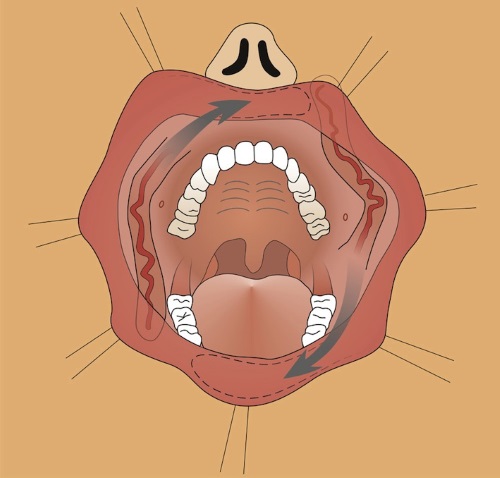

Пациентка Л. 27 лет с утратой нижней губы вследствие некротической формы рожистого воспаления. Полностью отсутствуют ткани нижней губы, обнажен подбородочный выступ нижней челюсти. Восстановление кожного покрова утраченной нижней губы проведено дермотензионным кожно-подкожным субментальным лоскутом. Восстановление слизистого слоя утраченной нижней губы проведено путем билатеральной пластики мышечно-слизистыми лоскутами на лицевой артерии с нижним основанием.

Пациентка Л. 27 лет. Восстановление утраченной нижней губы комбинацией дерматензионного субментального лоскута и двух билатеральных FAMM лоскутов с нижним основанием. Раневой дефект при поступлении в клинику. Этап дермотензии субментального лоскута.

Пациент С. 56 лет. Утрата тканей правой половины верхней губы и части верхней челюсти вследствие онкологического процесса.

Восстановление утраченного кожного покрова проведено путем использования дермотензионного субментального кожно-подкожного лоскута, а восстановление слизистого слоя верхней губы выполнено правосторонней пластикой FAMM лоскутом с верхним основанием.

Сформированный FAMM лоскут, перемещение в зону дефекта. Субментальный кожно-фасциальный лоскут, перемещение в зону дефекта.

При тотальных дефектах губ перечисленные выше методики не позволяют решить проблему восстановления утраченных тканей. В подобных случаях необходима комбинация лоскутов, формирующих наружную часть губы и слизистый слой. Ранее для реконструкции использовался щечно- слизистый лоскут, который был в определенным смысле прототипом FAMM лоскута, описанного Pribaz в 1992г. FAMM лоскут отличается от своего предшественника в части ориентации и артериального питания. При использовании лоскута для реконструкции губ, он имеет преимущество по сравнению с другими лоскутами в том, что операция проходит в один этап, а косое расположение делает его более податливым для перемещения в область планируемой реконструкции. Лоскут имеет довольно большую толщину, что позволяет создать адекватный объем губы, а сравнительно небольшая ширина позволяет свести к минимуму деформацию донорского места. Кроме того, косая ориентация лоскута благоприятна для функции мимических мышц. После купирования послеоперационного отека существенные нарушения мимики лица не определяются.